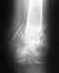

При 8-летней давности проблемы, боюсь, семейно-домашними возможностями не обойтись. Надо обращаться в ортопедо-травматологическое отделение, в котором выполняют мобилизующие операции (пластику 4-главой мышцы, артролиз и т.д.) в подобных ситуациях.